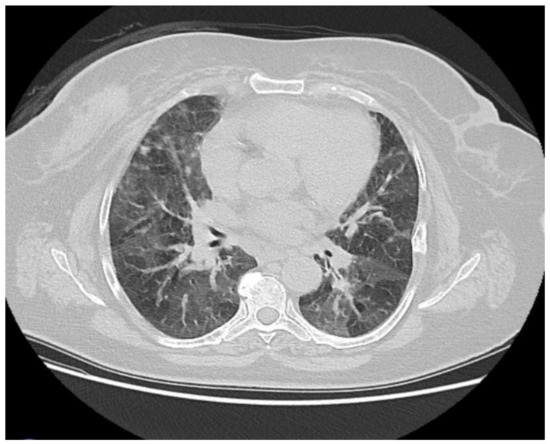

| Patient 3 | Hypersensitivity | Ribociclib | Bilateral lobe, air |

| Pneumonitis (HP) | trapping, | ||

| centrilobular | |||

| nodules, and | |||

| ground-glass | |||

| opacities. (Figure 2) | |||